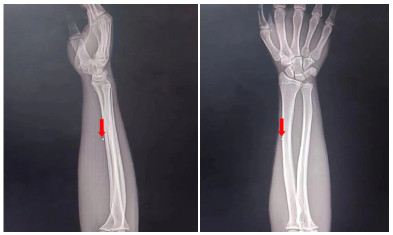

1 资料与方法患者男性,17岁,因“左前臂异物8 h”于2022-05-23 21:25收住急诊抢救室。患者8 h前修车时敲打金属物品,小片金属飞溅至左前臂,伴少量出血,无麻木等不适主诉。后立即于当地医院就诊,X线示异物位置如图 1,当地医院建议转上级医院。上级医院再次行X线检查(图 2),后予以臂丛麻醉下行“左上肢清创+异物取出术”术中未见异物,术后复查X线,左上肢,左肩部以及左侧胸部未见异物,嘱立即转至本院。

| 图 2 外伤后第二次评估异物位置X光检查图像 |